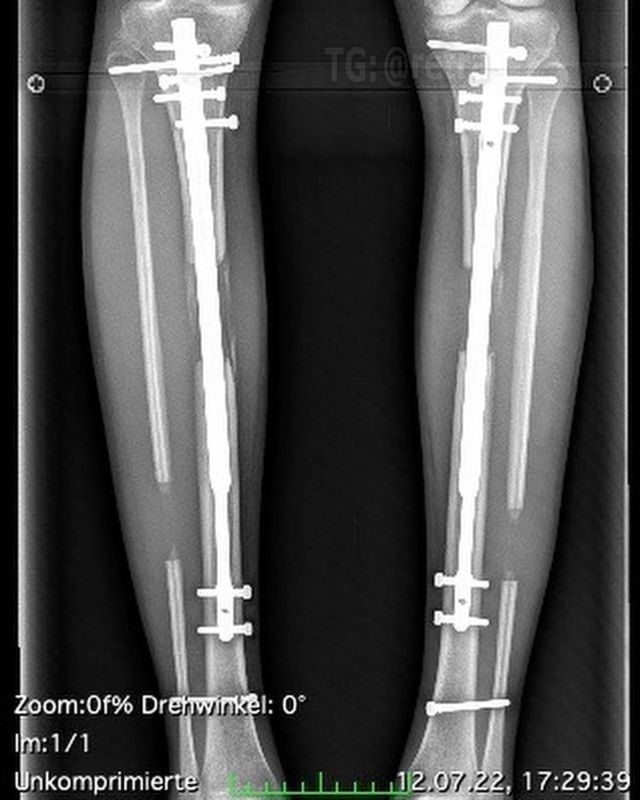

Процесс удлинения ног требует болезненной процедуры, при которой врач ломает кости в каждой ноге пациента и вставляет регулируемые телескопические стержни. В течение следующих трёх месяцев ноги постепенно удлиняются на один миллиметр в день, что в конечном итоге делает человека на несколько сантиметров выше.

Операция также влечёт за собой длительный процесс восстановления с «непрекращающейся» болью из-за растяжения нервов, мышц и тканей ног.